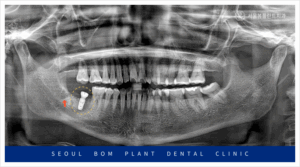

뼈이식 2달 후, 파노라마 촬영을 통해

발치 부위에 하얗게 뼈가 차오른 것을 확인한 후,

임플란트 식립을 진행하였습니다.

오금역치과 서울봄플란트에서는 임플란트 식립 전,

파노라마와 3D CT 촬영을 통해 환자의

구강 상태를 꼼꼼하게 검진했습니다.